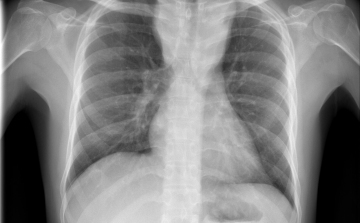

Egy líbiai menekülttáborból érkezhetett Európába a tbc egy új kórokozója

Menekültek révén, egy líbiai táborból érkezhetett Európába a tuberkulózis (tbc) kórokozójának egy korábban ismeretlen, gyógyszerekkel szemben ellenálló fajtája - írta a Die Welt című német lap a hírportálján szerdán.